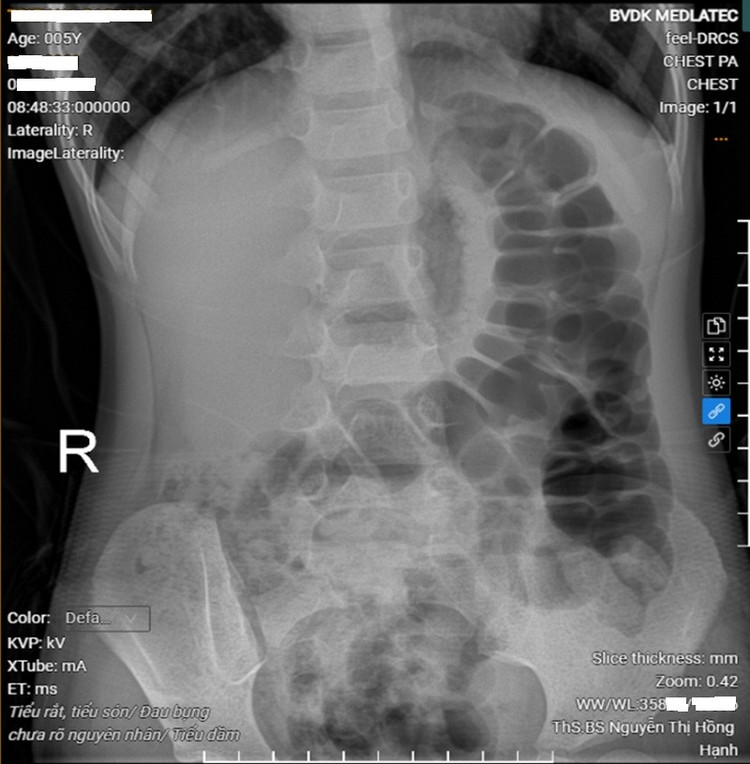

Kết quả xét nghiệm cho thấy, các chỉ số máu trong giới hạn bình thường, không có dấu hiệu nhiễm trùng; xét nghiệm nước tiểu bình thường, loại trừ nhiễm khuẩn đường tiết niệu. Siêu âm ổ bụng hiện tại chưa thấy có bất thường của đường tiết niệu. Hình ảnh X-quang ổ bụng, ghi nhận nhiều quai đại tràng giãn, chứa hơi và phân, gợi ý tình trạng ứ phân đại tràng do táo bón chức năng.

Hình ảnh chụp X-quang ổ bụng của bệnh nhi thấy nhiều quai đại tràng giãn, chứa hơi và phân. Ảnh Medlatec

Từ các kết quả đó, bác sĩ nghĩ nhiều đến tình trạng táo bón, ứ phân kéo dài có thể chèn ép bàng quang, làm giảm dung tích chứa nước tiểu và gây rối loạn phản xạ tiểu tiện, dẫn đến tiểu dầm, tiểu rắt và tiểu són kéo dài ở trẻ nhỏ.